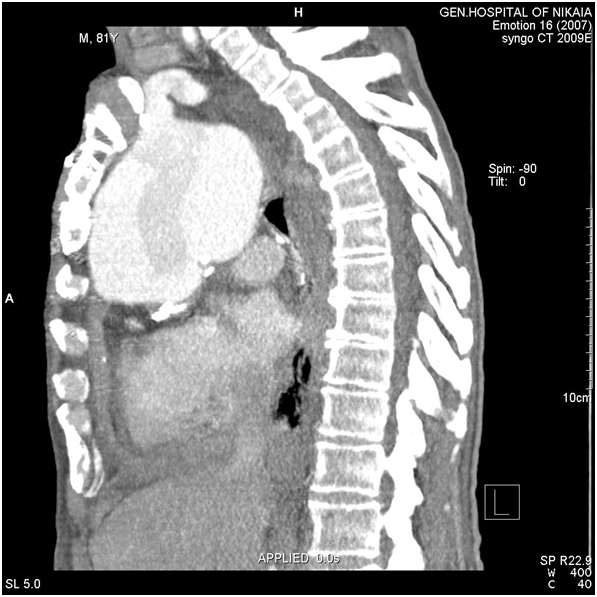

Due to patient’s history, a CT-angiography was immediately performed, which showed a massive perigraft aneurysm, 9x9.5 cm in maximum diameter, extended to the arch, compressing superior vena cava (SVC), brachiocephalic artery, right coronary artery (RCA), and graft partially detached from distal anastomosis, but within the aneurysmal sac Figure (2-7). The aneurysm was probably formed by a leakage at distal anastomosis, between the graft and the native aortic wall which was wrapped around it. A large right pleural effusion was also obvious. However, active leakage of the contrast agent from aneurysmal sac to the surrounding tissues was not observed at that point.

Figure 2 CT-angiography revealed a massive perigraft aneurysm, 9x9.5 cm. Superior vena cava compression (white arrowheads) and right pleural effusion are also manifested.